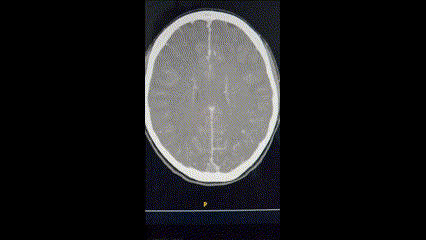

Le CT cérébral révèle la présence d’une thrombose veineuse étendue du sinus sagittal supérieur, du sinus transverse et sigmoïde droits, ainsi que de la veine jugulaire droite.

Le diagnostic est établit par imagerie cérébrale de type angio-CT cérébral injecté au temps veineux.